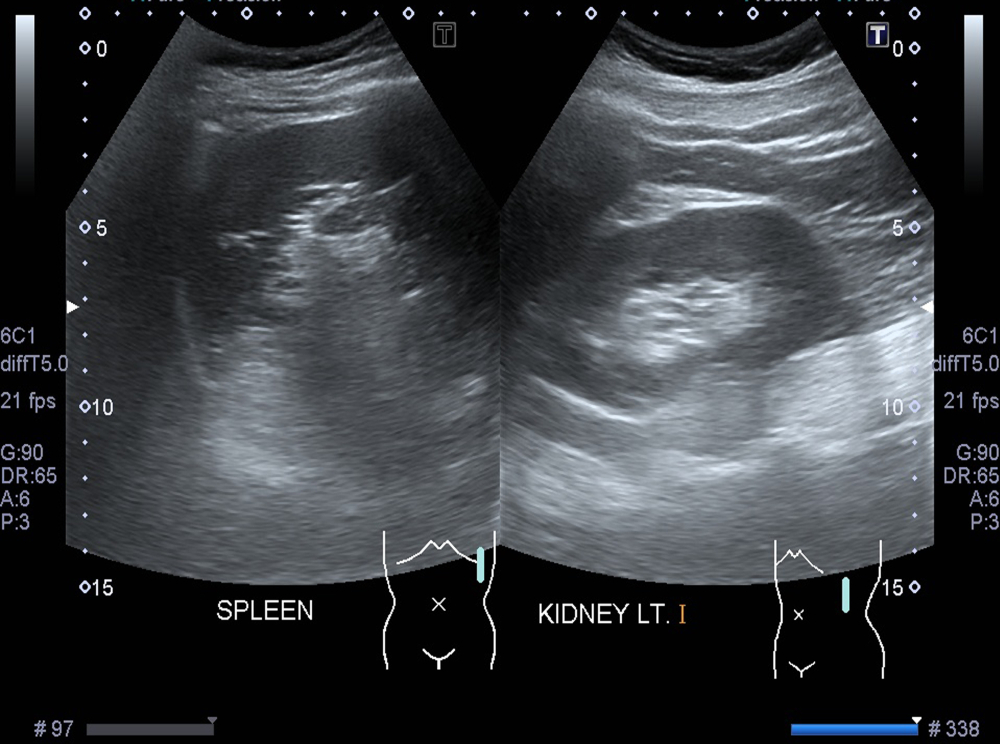

Расшифровка результатов

В протоколе указывают особенности сосудистого рисунка, если проводили оценку кровотока. В норме селезенка имеет четкие и ровные контуры, обычную форму, однородную структуру без грубых включений и деформаций. Ее эхогенность сопоставима с нормальной тканью соседних органов, капсула выглядит ровной, без признаков повреждения. Врач оценивает длину (в норме 8-14 см), толщину (3-5 см) и ширину (5-7 см) органа, и именно по этим параметрам формулируют, есть ли увеличение. Данные размеры общие для пациентов обоих полов. При этом вес может отличаться. Норма селезенки по УЗИ у взрослых мужчин составляет 190-200 г, тогда как у женщин 150-155 г. Орган занимает обычное положение, не выглядит смещенным, сосуды без грубых изменений, рядом нет подозрительных узлов и скоплений жидкости.

Изменения могут выглядеть по-разному. Чаще всего на УЗИ выявить удается следующие варианты: